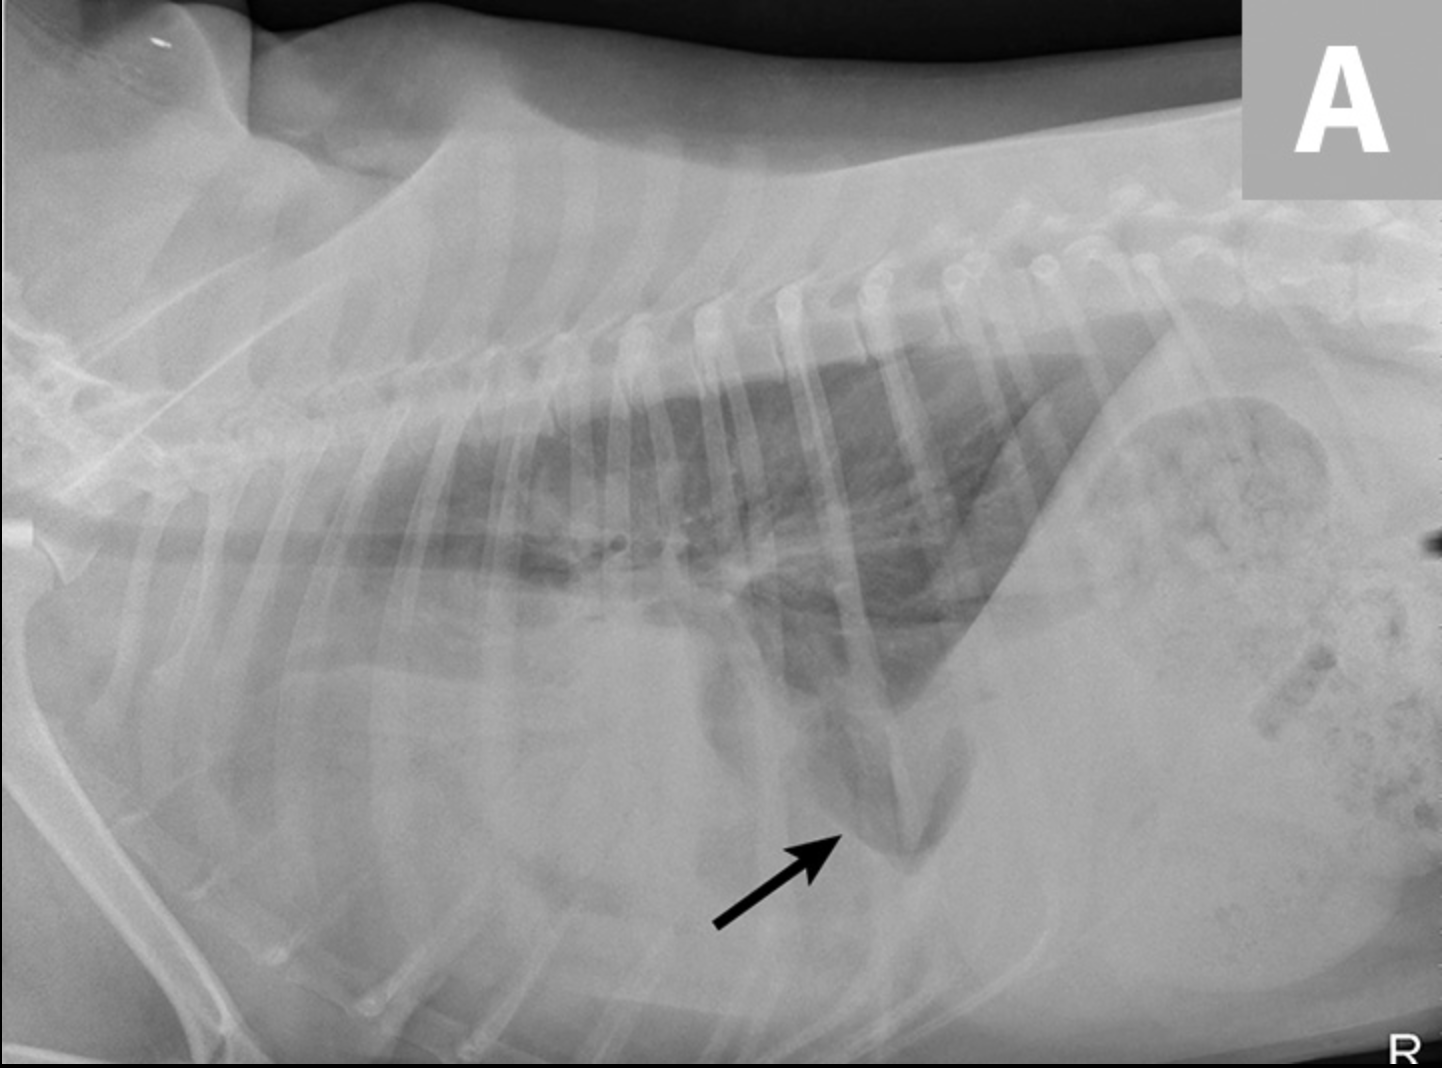

Las radiografías torácicas laterales derechas revelaron una gran cantidad de opacidad de líquido / tejido blando que oscurece la silueta cardíaca. Las radiografías ventrodorsales mostraron un aumento de la opacidad de los tejidos blandos en el hemitórax izquierdo, principalmente en los campos del pulmón craneal y medio. En el hemitórax izquierdo se observó un patrón intersticial leve, una línea de fisura pleural y borramiento del borde en el corazón (Figura 1).

Los hallazgos radiográficos sugirieron una combinación de enfermedad pulmonar y del espacio pleural. Los diagnósticos diferenciales incluyeron derrame pleural (p. Ej., Hemotórax, piotórax, quilotórax, hidrotórax, neoplasia) y la masa del espacio pleural o efecto de masa (p. Ej., Neoplasia, consolidación o torsión del lóbulo pulmonar, absceso / granuloma).